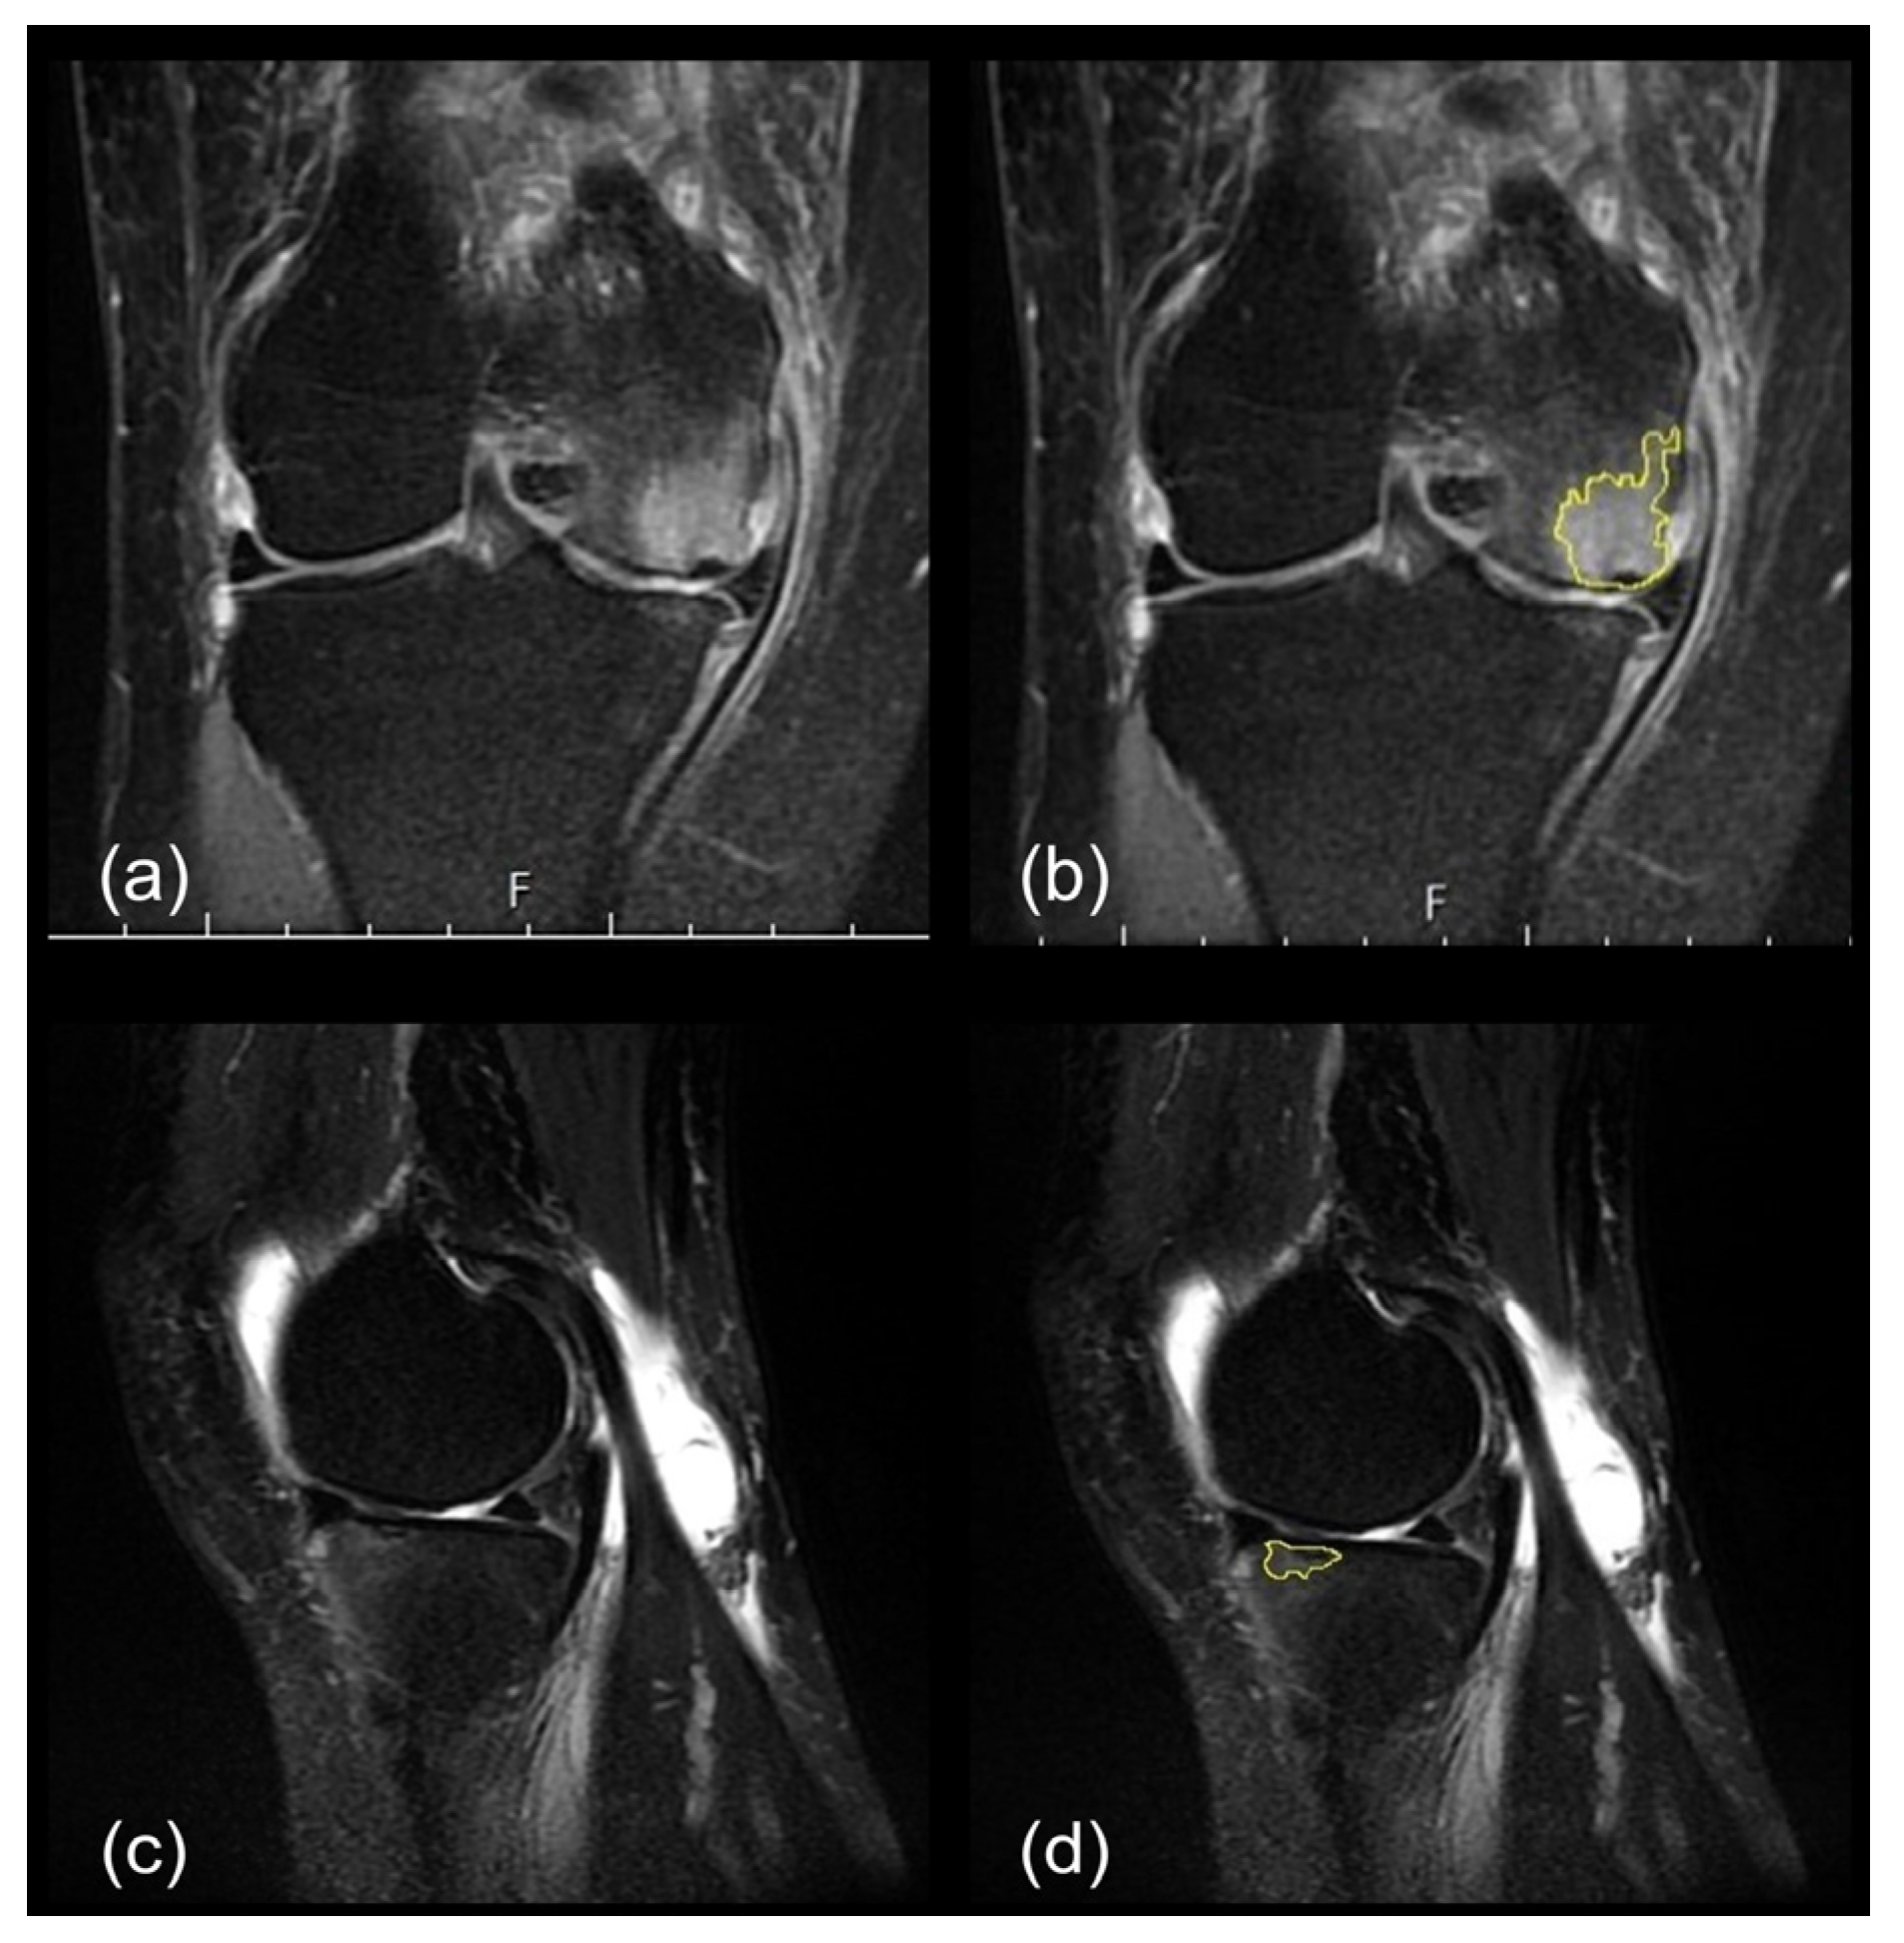

2.2.3. SIFK Identification